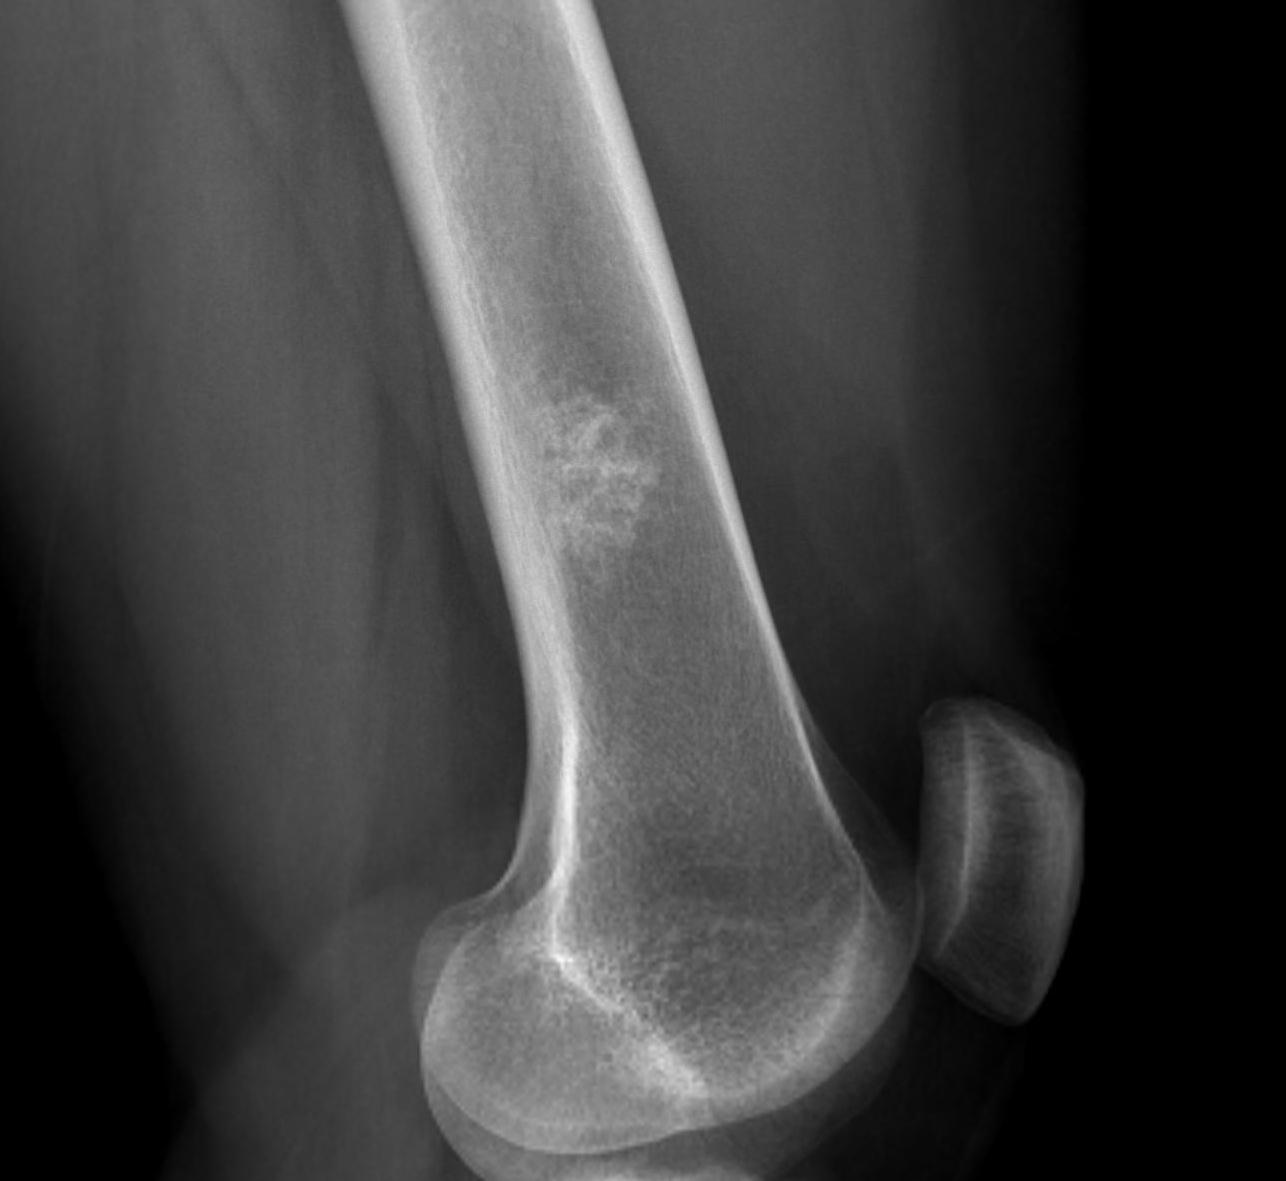

X-ray

Intralesional calcification - punctate, stippled calcification and broken rings

Endosteal scalloping

Large, central enchondroma